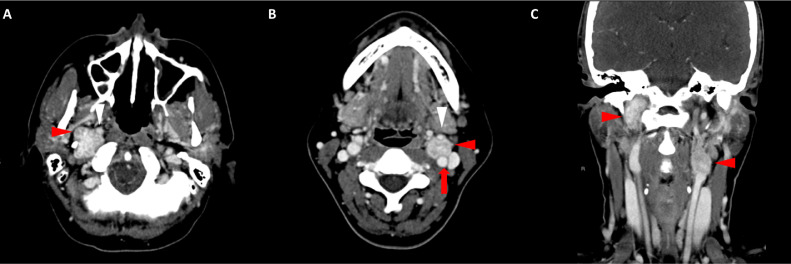

頸部增強(qiáng) CT 顯示 2 個(gè)強(qiáng)烈強(qiáng)化的腫塊。 一個(gè)位于頸部右側(cè),位于右側(cè)頸內(nèi)動脈后方的頸動脈間隙中,位于莖突內(nèi)側(cè),大小為 24 × 24 × 30 mm,頸靜脈橫向移位(圖 1A)。 第二個(gè)位于左側(cè)頸動脈間隙,在分叉處正上方展開頸外動脈和頸內(nèi)動脈,尺寸為 15 × 18 × 22 mm(圖 1B)。 影像學(xué)檢查結(jié)果與右側(cè)迷走神經(jīng)和左側(cè)頸動脈體副神經(jīng)節(jié)瘤一致,與之前的活檢結(jié)果一致。

Fig. 1

圖1:右側(cè)迷走神經(jīng)和左側(cè)頸動脈體副神經(jīng)節(jié)瘤。 (A) 軸位增強(qiáng) CT 顯示右側(cè)頸動脈間隙、右側(cè)頸內(nèi)動脈后方(白色箭頭)和莖突內(nèi)側(cè)有強(qiáng)烈強(qiáng)化的腫塊(紅色箭頭)。 (B) 軸位對比增強(qiáng) CT 顯示左頸動脈間隙有強(qiáng)烈強(qiáng)化的腫塊(紅色箭頭),向后張開頸內(nèi)動脈(紅色箭頭),向前張開頸外動脈(紅色箭頭)。 (C) 冠狀對比增強(qiáng) CT 顯示兩個(gè)增強(qiáng)腫塊(紅色箭頭)。